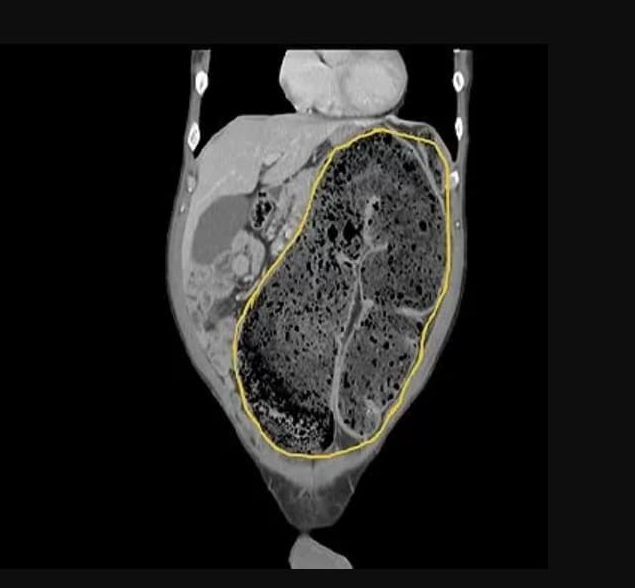

20일이 지나도 변을 보지 못해 심장 앞까지 변비가 꽉 찬 남성의 CT 사진이 올라와 보는 이들에게 엄청난 충격을 주고 있다.

최근 중국 의과대학 신주부속병원 페이스북 계정에 58세 남성 A씨가 20일 넘게 변을 보지 못해 이 병원 응급실로 실려갔다.

대장직장외과 전문의인 장주헝 박사가 이 남성을 진찰한 결과 장에는 배출하지 못한 변들이 모여 딱딱하게 굳어 장폐색이 온 상태라고 전했다.

특히 장 끝부분 S상 결장에 변이 계속해서 차올라 거의 심장까지 올라가 있어 모든 의료진들이 놀라움과 충격을 받았다.

더욱 더 놀라운 것은 장에 꽉 찬 변의 무게만 5kg가 넘었다.